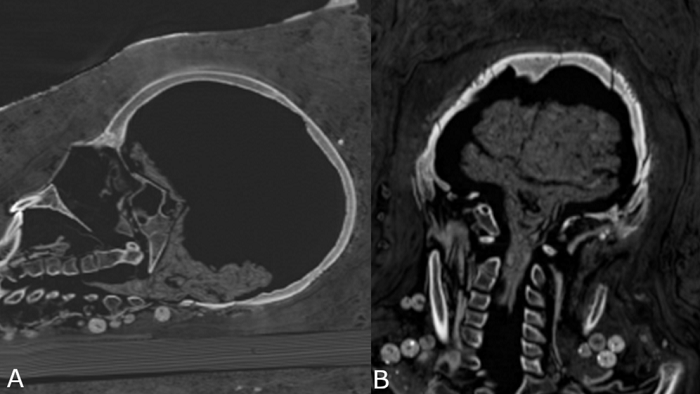

Mediante análisis de tomografía computarizada, los investigadores lograron obtener información sobre el estado de conservación de los cuerpos, la técnica de momificación artificial usada, la edad de los individuos en el momento de la muerte, así como su género, altura y salud.

"Las investigaciones radiológicas anteriores de las momias de los periodos romanos ya revelaron que algunas no mostraban evidencia de extirpación del cerebro y de los intestinos. La identificación del cerebro conservado en el caso de la mujer joven apoya, por lo tanto, esta idea", explicó a IFLScience, el investigador principal del estudio, Stephanie Zesch.

Este nuevo tratamiento fue posible identificarlo sólo en la momia joven, pues los cuerpos del hombre y la otra mujer estaban "bastante mal conservados" y no se pudo determinar una técnica específica de momificación artificial.